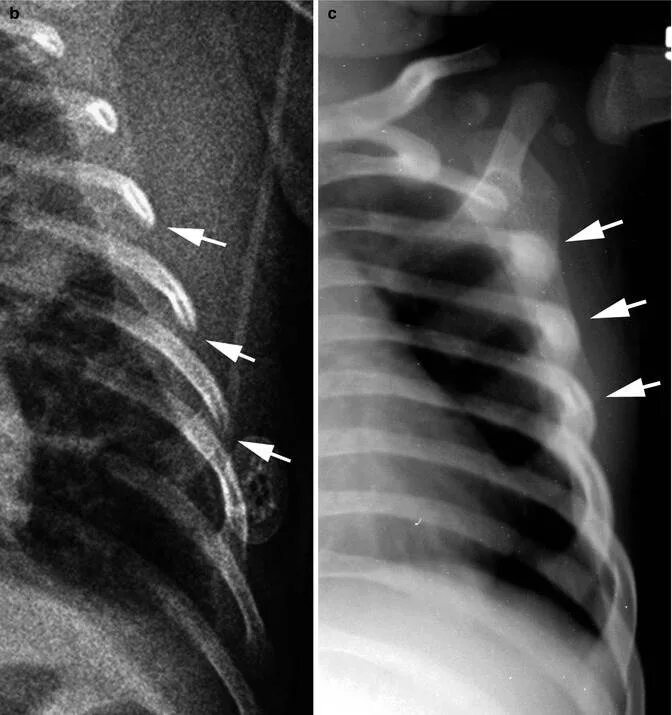

Как определить перелом ребра или ушиб